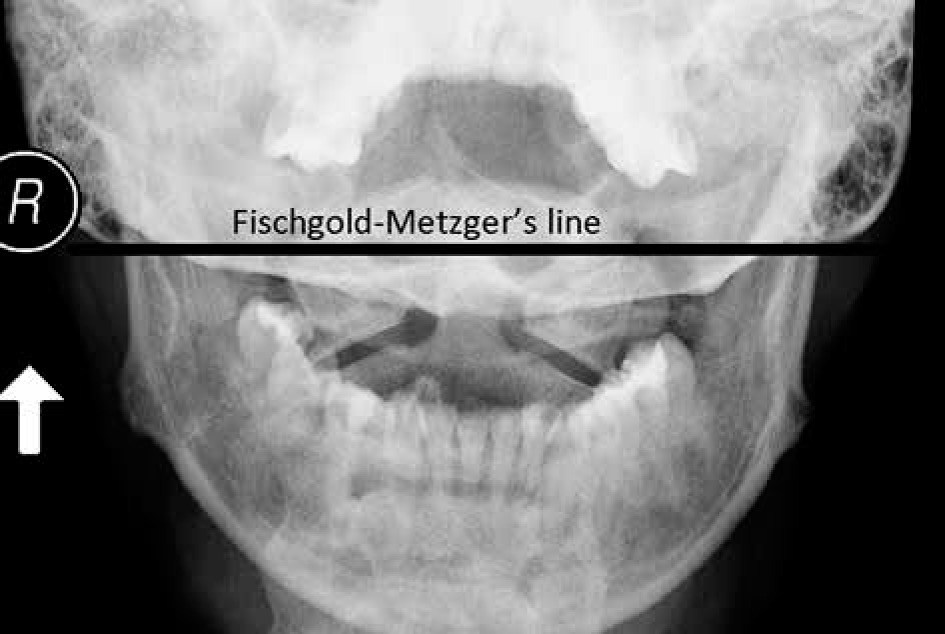

Another view used in rheumatology is AP projection with an open mouth, which is used to assess C1-C2 alignment and dens (Figure 1). However, in current practice, this view is rarely performed because it has been replaced by MRI and CT, which allow for a precise evaluation of this complex anatomical area. The significant limitation of plain radiography of the craniocervical junction is the superimposition of anatomical structures, which is especially common when rotational instability is present.

Figure 1

AP open mouth projection: Fischgold-Metzger’s line – example of measuring vertical subluxation

| Fischgold-Metzger’s line [40] | Line between mastoid processes on AP open mouth view | Apex of dens is above the line |